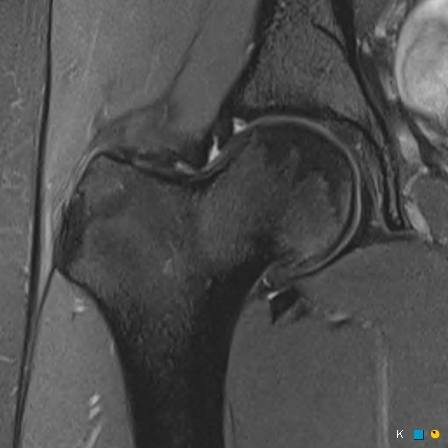

Figure 1 for case reverse slipped upper femoral epiphysis

Figure 1